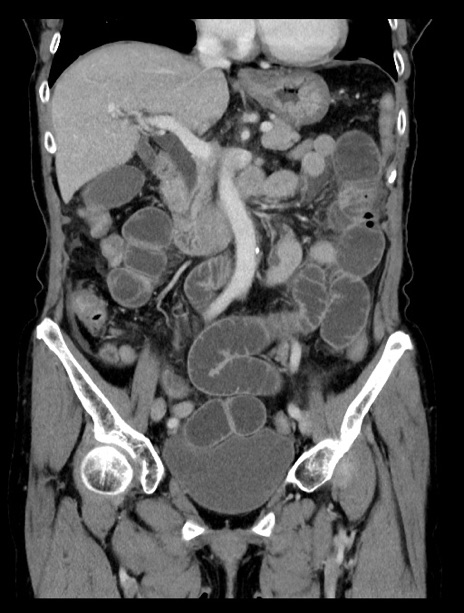

症例23(冠状断像)

【症例】70歳代女性

【主訴】下腹部痛・嘔吐

【現病歴】2日前より腹痛あり。昨日嘔吐あり。症状改善しないため来院。

【既往歴】胃GISTに対して胃部分切除後。

【身体所見】BT 37.1℃、BP 128/77mmHg、腹部:平坦・軟、下腹部に圧痛あり。

【データ】WBC 10200、CRP 0.31

横断像